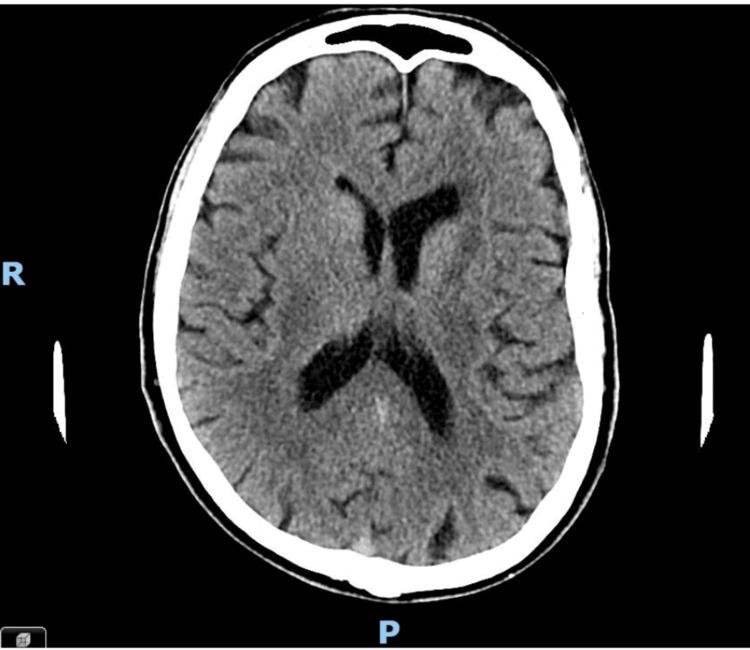

Cognitive impairment in the elderly is often attributed to neurodegenerative processes such as dementia or delirium. However, in some cases, structural brain lesions, including malignancies like glioblastoma and lymphomas, can present similarly. This case report is of a 79-year-old male with progressive cognitive decline who was initially suspected to have dementia but was later found to have a brain mass. The absence of focal neurological deficits and a normal initial CT scan delayed the recognition of an underlying malignancy. An MRI ultimately revealed a lesion concerning glioblastoma or primary central nervous system lymphoma (PCNSL). Given the patient's frailty, the neuro-oncology multidisciplinary team (MDT) recommended best supportive care rather than an invasive biopsy. This case underscores the importance of thorough assessment and neuroimaging in cases of unexplained cognitive decline and highlights the diagnostic pitfalls that can lead to misdiagnosis.

老年人的认知障碍通常归因于神经退行性过程,如痴呆或谵妄。然而,在某些情况下,包括胶质母细胞瘤和淋巴瘤等恶性肿瘤在内的脑结构病变也可能表现出类似症状。本病例报告的是一名79岁男性,其认知功能进行性下降,最初被怀疑患有痴呆,但后来发现有脑肿块。由于缺乏局灶性神经功能缺损且初始CT扫描正常,导致对潜在恶性肿瘤的识别延迟。最终MRI显示出一个可疑的胶质母细胞瘤或原发性中枢神经系统淋巴瘤(PCNSL)病变。鉴于患者身体虚弱,神经肿瘤多学科团队(MDT)建议采取最佳支持治疗,而非进行侵入性活检。该病例强调了在不明原因认知下降病例中进行全面评估和神经影像学检查的重要性,并突出了可能导致误诊的诊断陷阱。